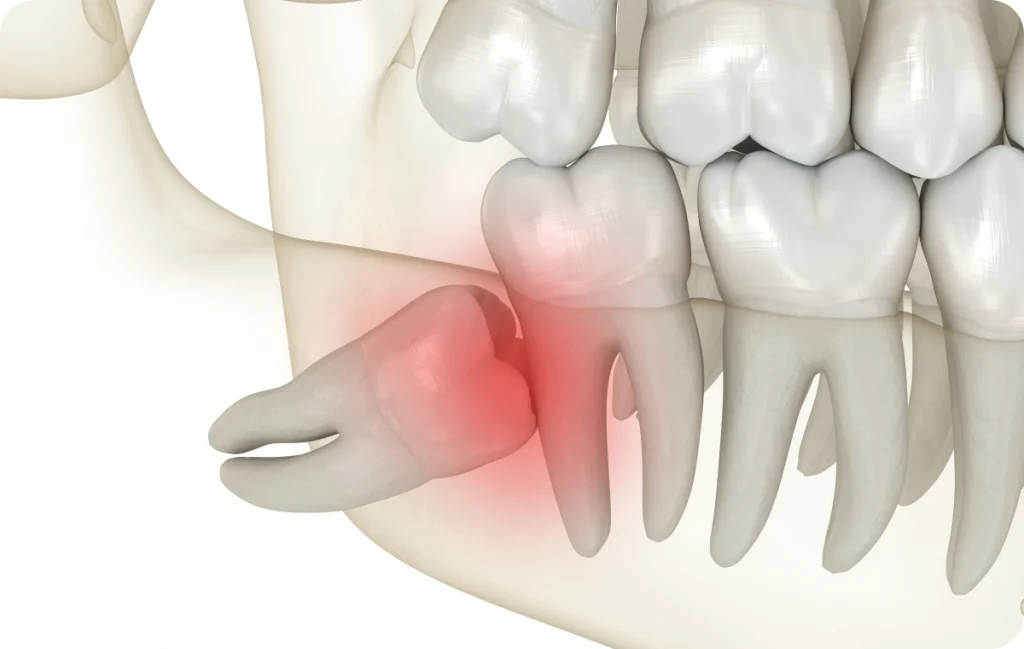

Le manque de place est l’une des causes les plus fréquentes de difficultés liées à l’éruption des troisièmes molaires. Lorsque l’espace est insuffisant, la dent peut rester coincée sous la gencive ou pousser de manière oblique.

Cette configuration crée des zones difficiles d’accès lors du brossage. Des résidus alimentaires et des bactéries peuvent alors s’accumuler, augmentant le risque d’inflammation gingivale. Cette inflammation peut se manifester par des douleurs, un gonflement ou une sensation de pression au fond de la bouche.

Dans certains cas, une dent mal positionnée peut également exercer une contrainte sur la molaire voisine, ce qui justifie une surveillance attentive.

Cas des dents semi-incluses

Lorsqu’une dent n’a percé la gencive que partiellement, on parle de dent semi-incluse. Cette situation favorise la stagnation bactérienne sous le capuchon gingival.

L’inflammation peut alors revenir de manière répétée. Une évaluation clinique et radiographique permet de déterminer la conduite à tenir.